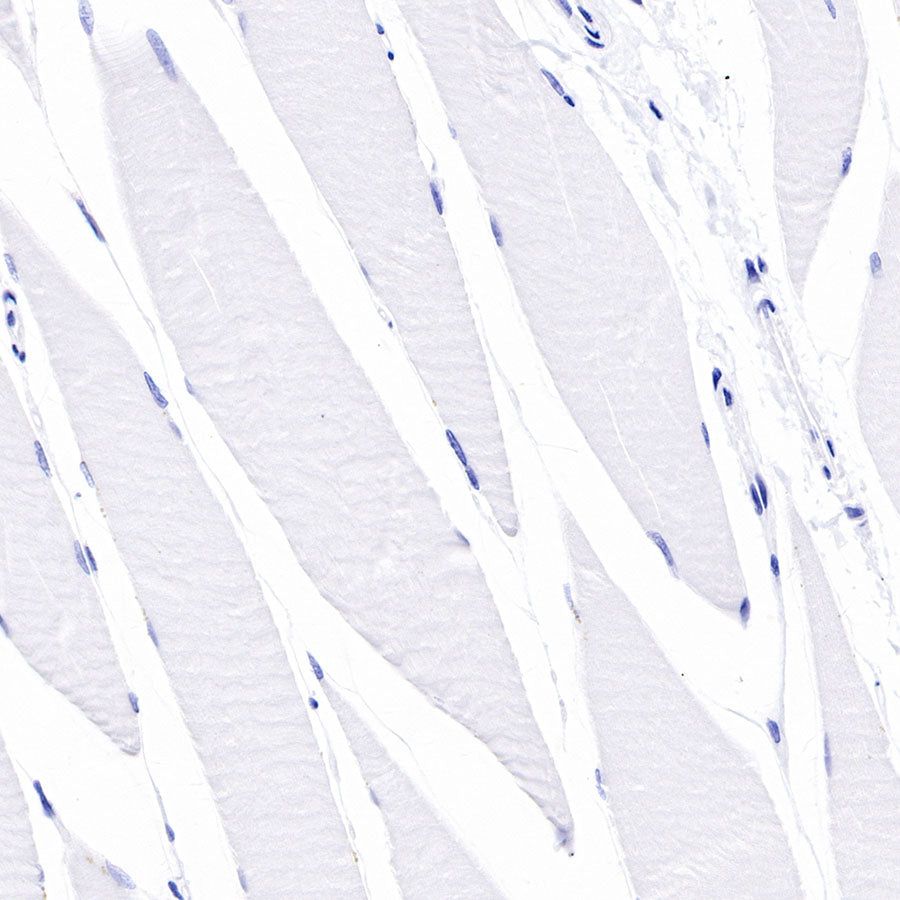

Immunohistochemistry